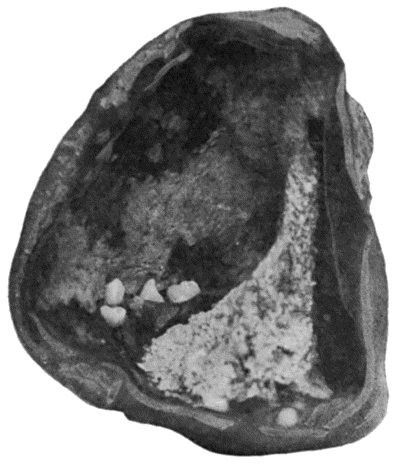

504 156.Caseating focus in Upper End of Fibula

513 157.Arthritis Deformans of Elbow